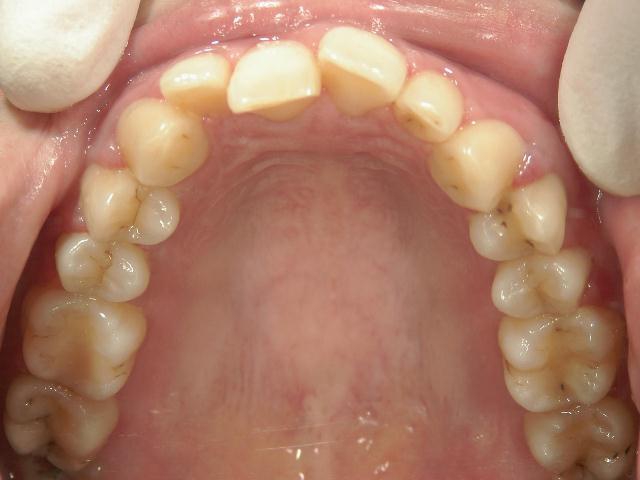

アクアシステム(透明マウスピース矯正)/上顎のみ 症例(1)

28歳 女性 浜松市中区在住  治療期間1年4ヶ月

矯正歯科 治療前 上顎